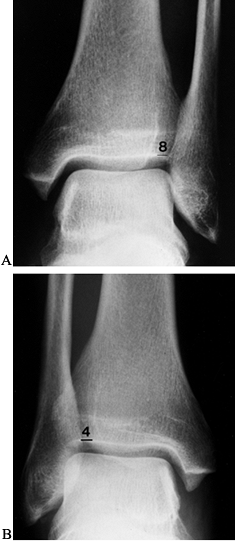

radiographs (Fig. 95.1 and Fig. 95.2).

to the posterior lip of the tibia. Talar tilt is measured as the degree

of angulation of the superior aspect of the talus as referenced against

the neutral position of tibial plafond.

| Figure 95.2. Abnormal stress radiographic talar tilt test (TTT) with more than 10° STSD: (A) injured ankle; (B) uninjured. |